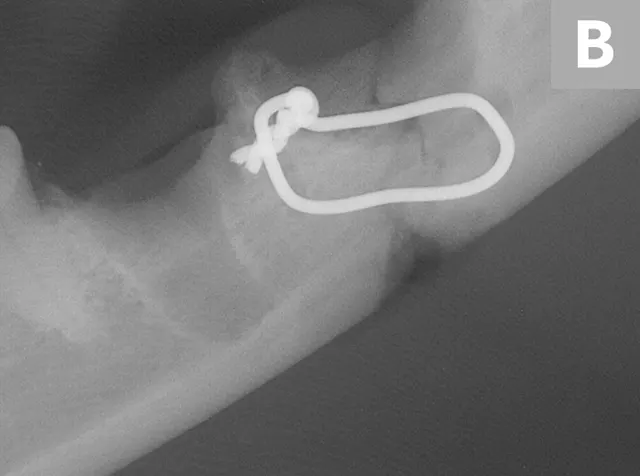

The patient was presented 7 weeks later for a recheck oral examination under general anesthesia (performed in the same manner as previously). Dental radiographs demonstrated healing of the fractures (Figure 4). The interfragmentary wires were removed via an intraoral approach, and postoperative intraoral radiographs were obtained to confirm adequate healing (Figure 5). The patient recovered uneventfully.

Postoperative intraoral dental radiographs of the right (A) and left (B) mandible following reduction and fixation with a single intraosseous wire on each side.